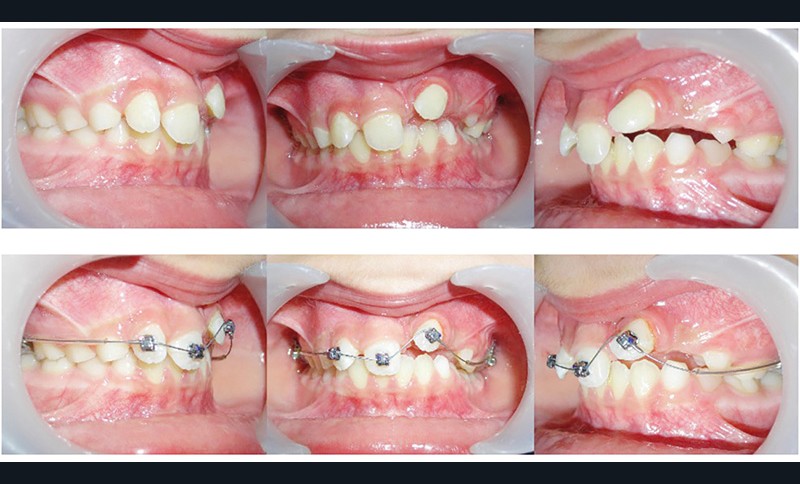

La 22 doit être remise sur l’arcade et le choix est fait de la mettre en lieu de 21 (fig. 4), puis de la maquiller pour temporiser en attendant l’évolution des autres dents définitives, et éviter le port d’une prothèse amovible transitoire (P.A.T.) tout en ramenant de l’os alvéolaire dans l’espace de 21.

L’interception dure 6 mois, et les attaches antérieures sont laissées en place et ligaturées (fig. 5) pour permettre une contention légère. On note la perte de la médiane.